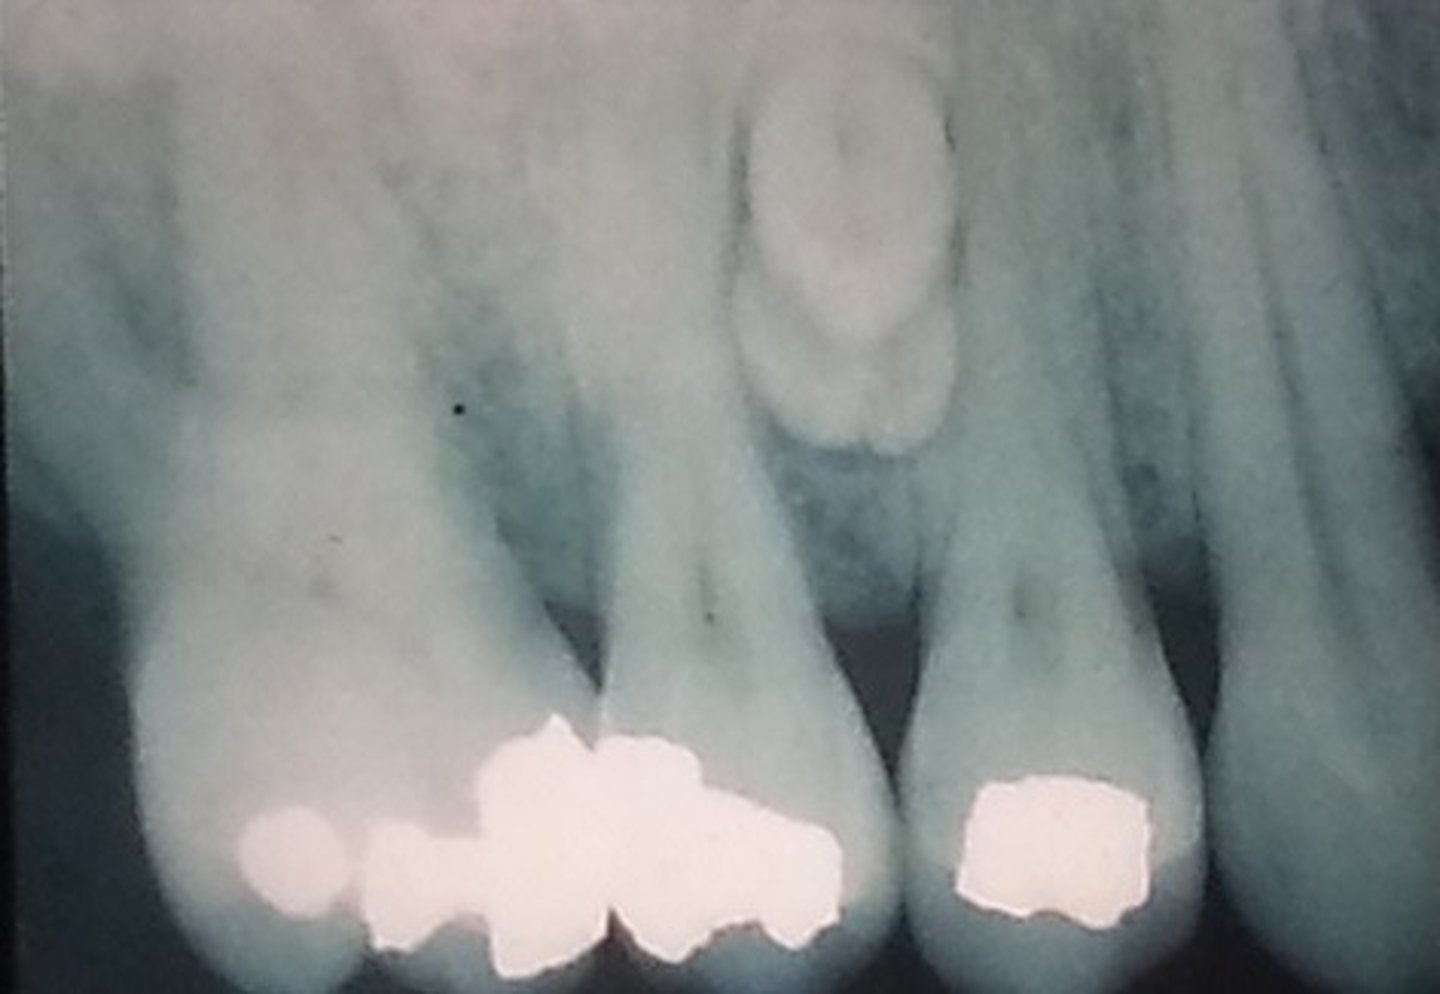

What is the radiographic appearance of compound odontomas?

cluster of miniature teeth (or extra mini tooth)

What is the treatment and prognosis for compound odontomas?

⢠treatment: surgical excision

⢠prognosis: excellent

What is the population of compound odontomas?

young: 10-20 yrs old